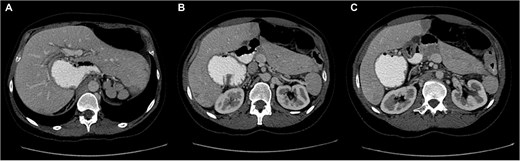

Laboratory investigations showed mild neutrophilic leukocytosis. Abdominal computed tomography (CT) with oral Gastrografin demonstrated marked gastric distension and mesenteric vascular swirling, suggestive of intestinal volvulus and raising suspicion of an underlying rotational anomaly (Fig. 1).

Sequential axial CT images following oral Gastrografin administration showing marked gastric distension and mesenteric vascular swirling, suggestive of volvulus in the setting of intestinal malrotation (A–C).